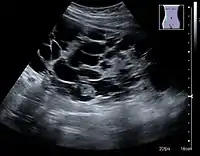

Complex cysts can have membranes dividing the fluid-filled center with internal echoes, calcifications or irregular thickened walls. The complex cyst can be further evaluated with Doppler US, and for Bosniak classification and follow-up of complex cysts, either contrast-enhanced ultrasound (CEUS) or contrast CT is used (Figure 6). The Bosniak classification is divided into four groups going from I, corresponding to a simple cyst, to IV, corresponding to a cyst with solid parts and an 85–100% risk of malignancy.[1] In polycystic kidney disease, multiple cysts of varying size in close contact with each other are seen filling virtually the entire renal region. In advanced stages of this disease, the kidneys are enlarged with a lack of corticomedullary differentiation (Figure 7).[1]